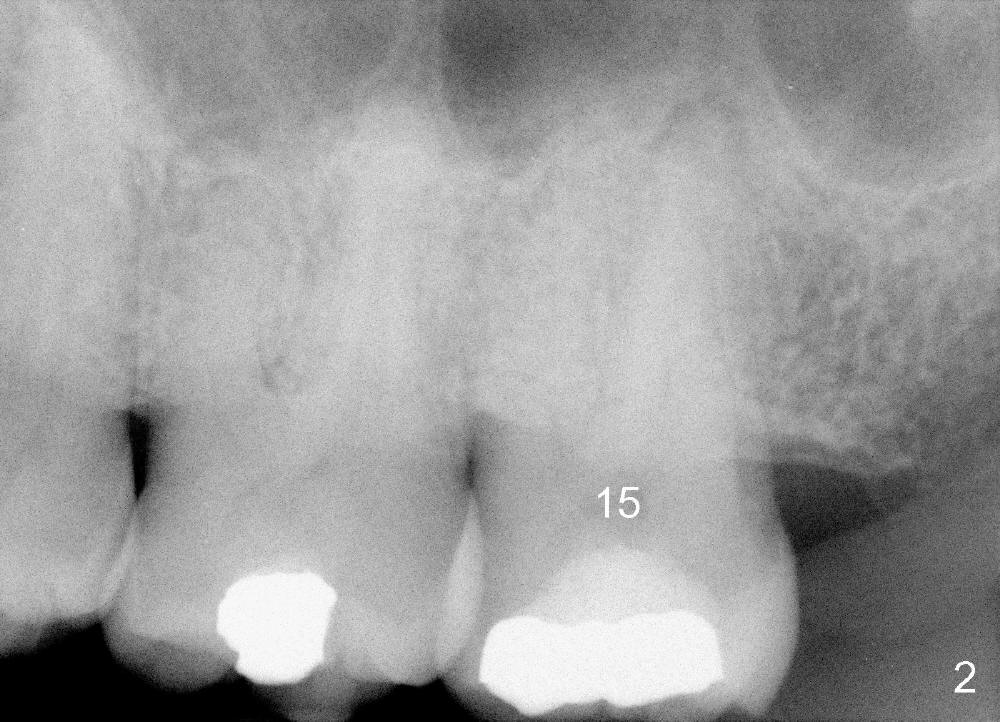

A 52-year-old black man fails to return to finish root canal therapy for the tooth #15; ultimately it is non-salvageable (Fig.1-3). The tooth has 3 basically fused roots (Fig.4 black (buccal) and red (palatal) outlines), above which is the sinus septum (*). By inserting an immediate implant into the sinus septum, primary stability should be high (Fig.5 vs. 6).